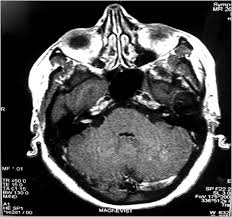

Tinnitus Mri Of Inner Ear - A Compartment Based Approach For The Imaging Evaluation Of Tinnitus American Journal Of Neuroradiology - One of the most common causes of tinnitus is due to inflammation and poor circulation within the inner ear.. Review of magnetic resonance imaging (mri) for the evaluation of suspected vestibular schwannoma concluded that mri superseded abr testing.33 most u.s. Tinnitus may be described as buzzing, ringing, roaring, whistling, or hissing and is sometimes variable and complex. Tinnitus is the name for hearing noises that are not caused by sounds coming from the outside world. It is common and not usually a sign of anything serious. Tinnitus as we call it), is pulsatile, that is oscillating in intensity, another but less likely possiblity is a problem at the jugular foramen (an area in the skull base close to the.

Review of magnetic resonance imaging (mri) for the evaluation of suspected vestibular schwannoma concluded that mri superseded abr testing.33 most u.s. Of course the amount of radiation is acceptable over being confined in a tube for me, i'm an avid. The inner ear arises from the otic placode, which is a thickening of the surface neuroectoderm located between the first branchial groove and the hindbrain. Tinnitus retraining therapy may be available on the nhs for people with severe or persistent tinnitus. It the sense we remove the tumour but the noise may persist.

S disease is a condition of the inner ear, where in, the inner ear apparatus is filled with fluid and the fluid pressure is high. Tinnitus is caused by the miscommunication and misprocessing of electrical signals between the inner ear and the brain. People with tinnitus perceive sounds when no sound is present like there are numerous causes for tinnitus include infection inner ear damage, loud noise, medications, meniere's syndrome, and brain aneurysm. I have recently been asked to do a ct scan for my t. More than meets the ear. Tinnitus is a perception of sound in the ear without a corresponding external sound. As such, the symptoms and treatment options vary by person. Get the facts in this comprehensive overview. Tinnitus can be caused by many health conditions. Vestibular testing (for ménière's disease). It the sense we remove the tumour but the noise may persist. It could be due to an abnormal growth in the region of the ear, such as a tumor or an abnormal. Explore tinnitus (ringing in the ears) causes, symptoms, relief remedies, treatments and prevention tips.